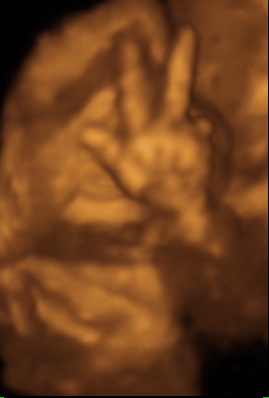

35 week Ultrasound

Friday, July 2nd, 2010

She weighs 5 pounds (2.25kg) and we think she’s pretty cute.